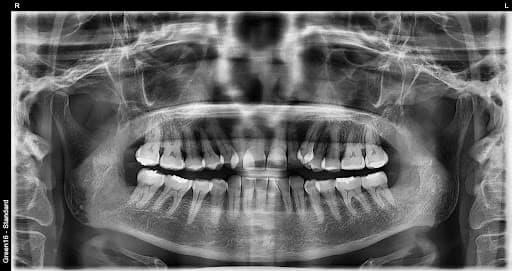

RISK LEVELS

Aql tishi holatiga qarab xavf darajasi

After

Past xavf

Oddiy aql tishi

Normal o'sgan aql tishi ham parvarish qilish qiyin bo'lgani uchun karies xavfi yuqori

O'rta xavf

Qisman ko'milgan aql tishi

Ovqat qoldiqlari yig'ilib qolishi oson va yallig'lanish tez-tez yuzaga keladi

Yuqori xavf

To'liq ko'milgan aql tishi

Kista hosil bo'lishi mumkin bo'lgani uchun erta sug'urib olish kerak

Ortodontiya davrida aql tishi

Ortodontiya davolash jarayonida aql tishini sug'urib olish zarur bo'lgan holat